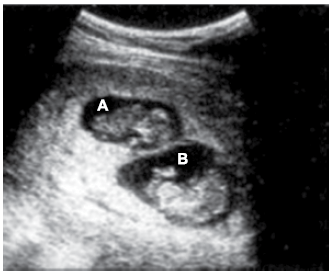

A presença de dois ou mais fetos na cavidade uterina define gestação gemelar (gestação de alto risco), cuja incidência tem aumentado graças a alguns fatores predisponentes, entre os quais a maior frequência e o melhor resultado dos procedimentos em reprodução humana assistida em idade mais avançada. Observe a imagem a seguir.

De acordo com a imagem, assinale a alternativa apresenta interpretação correta.